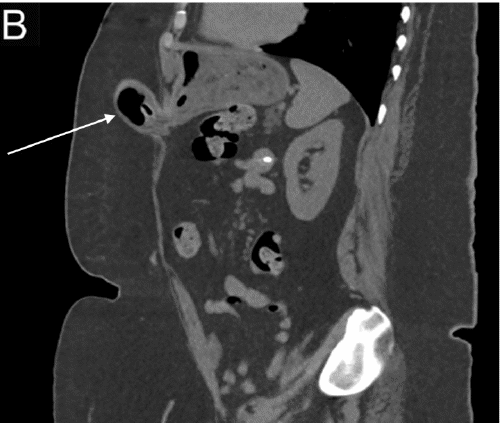

A computed tomography (CT) scan of the abdomen and pelvis revealed gastric herniation through a fascial defect associated with her gastrostomy tube (Figure 1). The stomach had no signs of stranding or ischemia to suggest strangulation, and there was no evidence of surrounding soft tissue edema.

Figure 1. CT Abdomen Without Contrast. Published with Permission

A) Axial slices demonstrating gastric hernia (arrow); the gastrostomy tube is visualized

B) Sagittal view demonstrating gastric hernia (arrow)